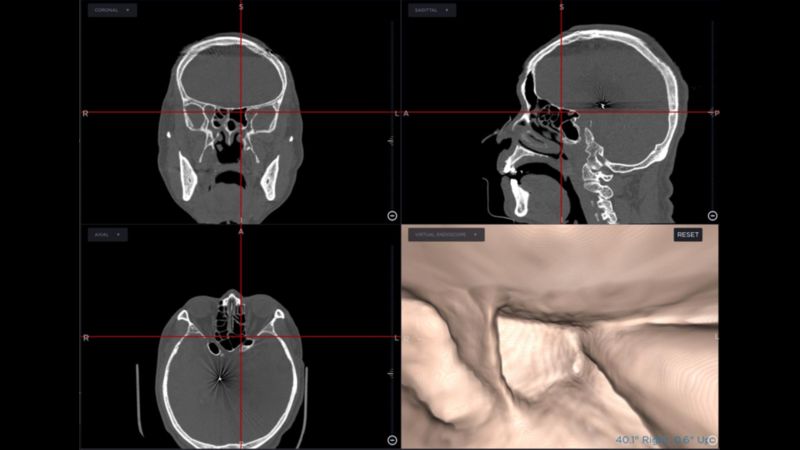

手術導航系統是利用患者的電腦斷層或核磁共振,製作出鼻竇附近的"google map",此地圖中呈現出病人鼻竇細微的解剖結構、病灶、及周遭所有之神經、血管、腦部及眼窩的影像。隨手術進行中,依手術器械所在位置,可即時出現器械鄰近的解剖影像及結構,如同在google map上即時呈現車子所在路況及周遭的建物。使用此系統,在鼻竇的細微且複雜的結構中,開刀時就降低迷路的風險;器械可精準切除病灶,避免傷害鄰近的重要器官,對於患者與醫療團隊都是一大利器。鍾得從主任以其使用手術導航系統十六年的經驗裡,不僅在復發之鼻竇炎、鼻息肉的內視鏡手術,並於鼻竇鄰近或腦部眼窩之病變,如黏液囊腫、顱底腫瘤、復發之鼻咽癌等手術中,藉由導航系統的精準定位,確實提高了手術的成功率及在病人的安全性上提供莫大保障。